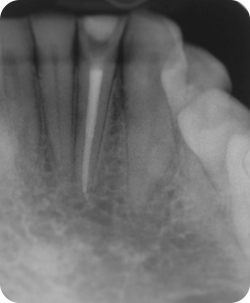

Original PA before Retreatment

Final Postoperative Radiograph

What prompted him to come in was the color of the tooth, so we discussed the need to have the endo redone despite the fact that no periapical pathology was seen but because it was open for so long. I suspect that they had IRM in the access, but the cotton pellet was still in the tooth.

Length control was ok not perhaps perfect but I think the end result for an easy case was decent.